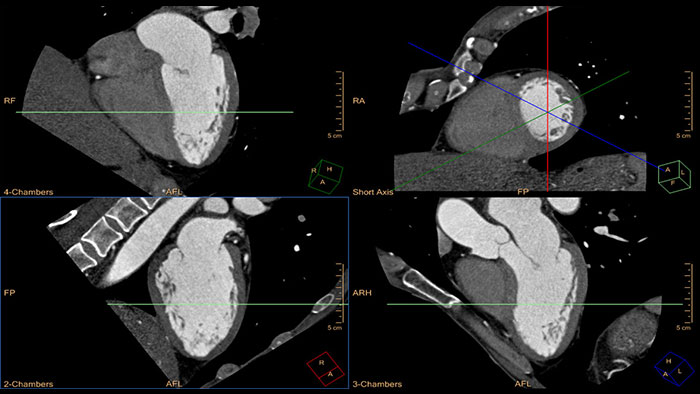

Comprehensive Cardiac Analysis (CCA)

CT Comprehensive Cardiac Analysis (CCA)

Comprehensive cardiac analysis

Designed to assist the user in viewing, analyzing and quantifying dedicated Cardiac CT Angiograms, mainly for coronary arteries analysis on Coronaries CT Angiogram (CCTA) data.

comprehensive cardiac analysis thumbnail

Benefits

• Cardiac function measurements based on automatic 3D model-based whole-heart segmentation.

• Automatic extraction and visualization of the coronary tree.

• The user can edit and modify the segmentation and the derived parameters.